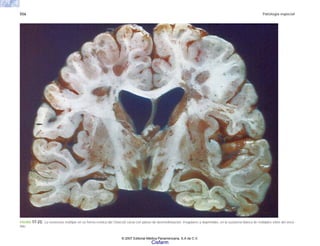

C7 Patología general de la circulación 127

FIGURA 7-7. Esquema de los mecanismos compensadores de la hemorragia.